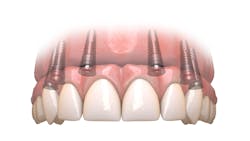

As a prosthodontist who has spent the last 25 years offering full-arch treatment to my patients and teaching the Hybridge full-arch protocols for most of that time, the phrase “Pick a Path” has come to refer to the difficult decision a patient makes to either commit to restoring their natural dentition or to replace their remaining teeth with a completely implant-supported prosthesis, as in a full-arch solution. The last decade has seen this implant modality gain in popularity.

Treatment objectives: Restore or replace all teeth to achieve full function and a natural, healthy-looking smile with a solution that is fixed and will last over the long term (20-plus years).

Today, more than ever, patients expect and hope their dental restoration will solve what has historically been a lifetime cycle of dental problems and expense. In this case, a straightforward, conventional restorative treatment plan that focuses on restoring the patient’s natural teeth may not make the most sense long term. After comparing both restorative paths, the full-arch implant option would likely prove to have a better prognosis, lower cost, and require much less time and fewer appointments.